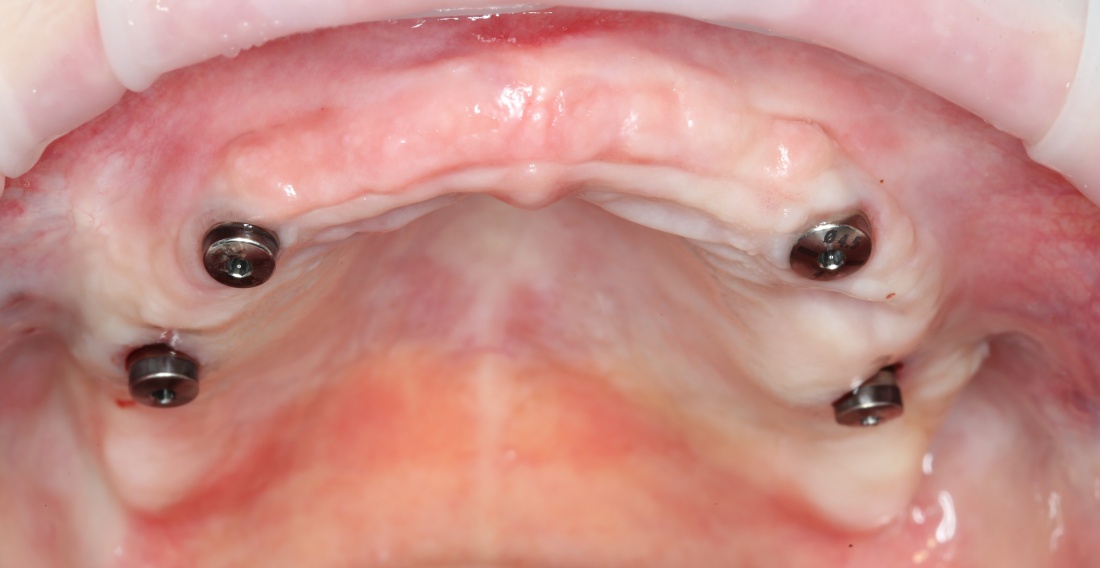

Рекомендации по установке имплантов. Для всех. Часть V.